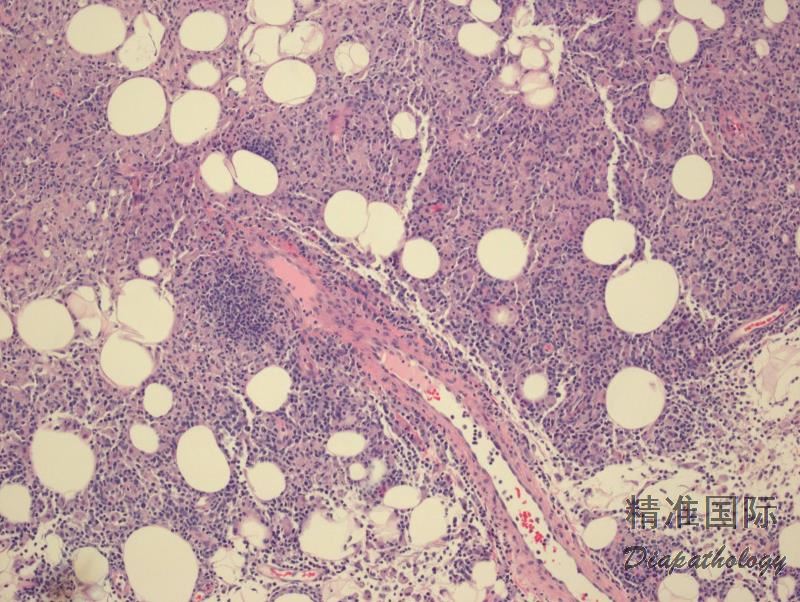

组织学上肿瘤细胞有 3 种浸润模式:亲表皮性,真皮和皮下。同一患者的不同部位或同一活检标本常见一种或多种侵润模式。表皮浸润可以是轻度或十分明显甚至呈现 Pagetoid 分布。皮下浸润时肿瘤细胞环绕脂肪细胞生长与 α/β 型 SPTCL 的相似,但同时有真皮和表皮浸润。常见血管浸润、细胞凋亡及坏死。